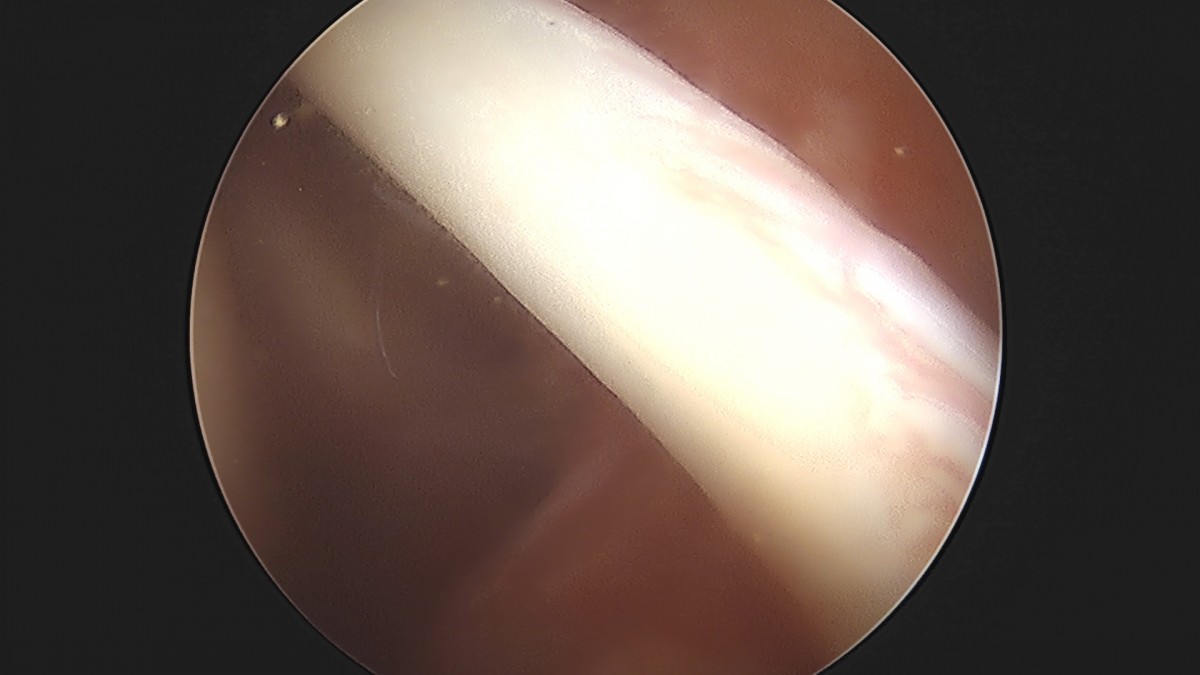

이재상원장님 어깨 견봉하 감압술 및 관절낭 이완술 양명O 환자

dae765e4d9ac96aee867c9d6292d8784_1758004381_4838.jpg